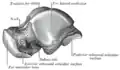

The neck of talus is directed anteromedially, and comprises the constricted portion of the bone between the body and the oval head.[8]

Its upper and medial surfaces are rough, for the attachment of ligaments; its lateral surface is concave and is continuous below with the deep groove for the interosseous talocalcaneal ligament.[8]

Left talus, medial surface